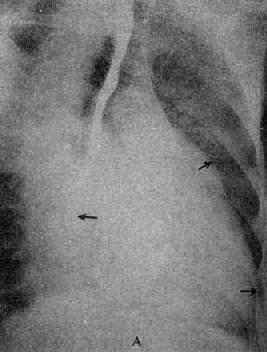

图3-2-15 二尖瓣狭窄

A.右前斜位:右心室增大,肺动脉段突出(↑),心前间隙变窄(↑),左心房轻度增大;B.后前位:心增大,呈二尖瓣型,右心室增大,肺动脉段突出,左心耳增大,出现第三弓(↓),有肺瘀血表现;C.左前斜位:右心室增大,左心房增大不明显;左心室不增大。